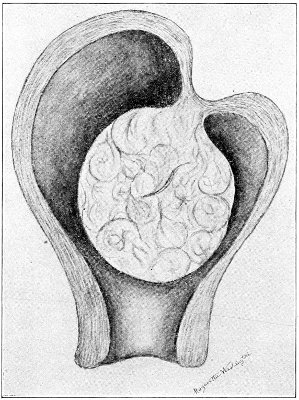

Cysts of the gland may be unilocular if formed at the expense of a single lobule of the gland, or multilocular if several lobules enter into their formation. These cysts may attain the size of the fetal head (Fig. 18).

Cysts of the gland or of the duct are formed by retention of the cyst-contents. The retention is due to occlusion of the duct, usually the result of inflammation. In some cases the duct remains pervious, and the retention is due to the altered character of the secretion of the gland, which becomes too viscous to pass, except under unusual pressure, along the duct.

These cysts contain clear yellow or chocolate-colored 42 fluid. The diagnosis of cyst of the vulvo-vaginal gland is usually not difficult. If we are in doubt in regard to the fluid character of the tumor, this may be determined with the exploring-needle.

Inguinal hernia, hydrocele of the canal of Nuck, cysts of the round ligament, and sacculated cysts of old hernial sacs may be mistaken for cysts of the vulvo-vaginal glands. In such cases, however, the tumor lies more in the upper and outer part of the labium majus, and extends to, and may be connected with, the external inguinal ring.

Cysts of the vulvo-vaginal glands should be treated by free incision and packing, or by extirpation. If the sac is emptied by the aspirator or by a small incision, it will refill. The best method is to extirpate the cyst. In case there has been no inflammatory action binding the cyst to surrounding structures, extirpation without rupture is easy. If rupture occurs, the cyst-wall may be dissected off with the knife or removed with the curved scissors. The wound may be immediately closed with deep and superficial sutures.